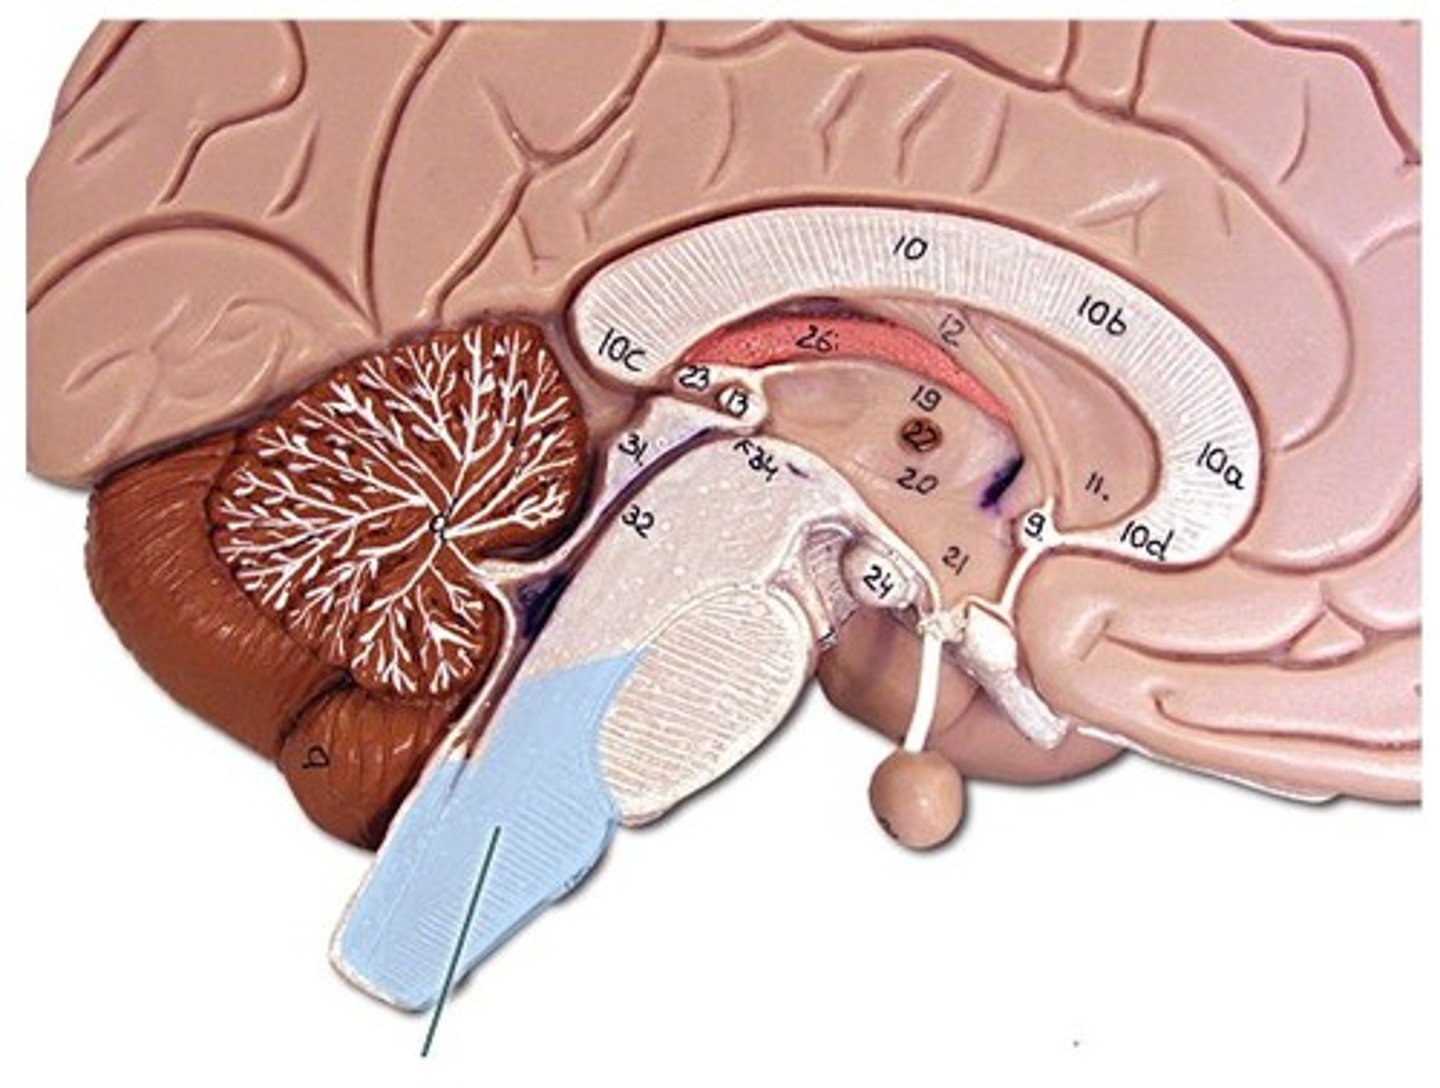

Brain Stem

1) Attaches to the spinal cord with no change in structure.

2) Only 2.5% of total brain mass but integrates many vital function.

3) Histologically similar to spinal cord (gray matter surrounded by white matter) but has nuclei of gray matter embedded in the white matter (which is not seen in cord).

4) Provides pathway for fiber tracts running between higher and lower neural centers and associated with 10 out of 12 pairs of cranial nerves.

Parts of the Brain Stem

Midbrain,

Pons,

Medulla Oblongata

Midbrain

Composed mostly of tracts of nerves fibers

Cerebral Aqueduct

Pons

Includes nuclei involved in the control of breathing

Medulla Oblongata

1) Most inferior part of the brain steam.

2) Merges into spinal cord.

3) Includes important ascending & descending nerve tracts.

4) Autonomic control center for heart rate, blood pressure, breathing, swallowing, coughing, sneezing, vomiting

Cerebellum

Two hemispheres with convoluted surfaces,

Accounts for ~11% of total brain mass,

Provides involuntary coordination of body movements,

Also plays a role in posture and equilibrium

4th Ventricle

Cerebrospinal Fluid (CSF)

1) Formed by choroid plexus in each ventricle.

2) Similar to blood but no red blood cells and much lower protein level.

3) Supplies nutrients and forms protective fluid cushion that gives buoyancy to CNS structures:

-Reduces brain weight by ~97% and prevents it from crushing under its own weight (very delicate)

4) Circulated in subarachnoid space, ventricles, and central canal (facilitated by ependymal cells that line each of these areas)

Ventricles

1) Right & left lateral ventricles:

-Anterior, Posterior & inferior horns

2) 3rd Ventricle, Cerebral aqueduct, 4th ventricles

4) Apertures (Narrow openings) into subarachnoid space of spinal cord